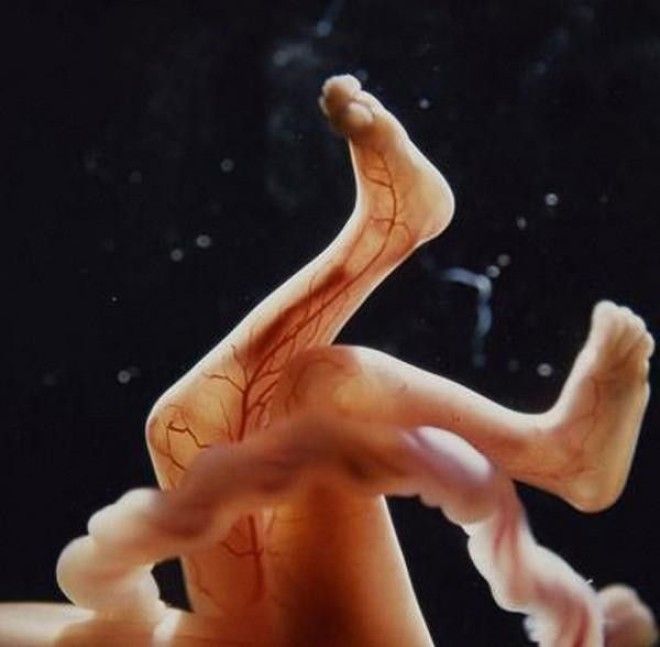

Сквозь тонкую кожу видна сеть кровеносных сосудов

18 недель. Зародыш может воспринимать звуки из внешнего мира